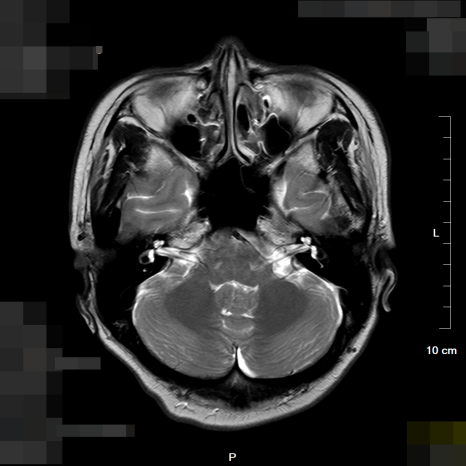

(좌) 3cm크기의 종괴 소견 뇌MRI / (우) 정상 소견의 뇌MRI

정밀 뇌 MRI 검사 결과, 환자분의 소뇌를 강력하게 누르고 있는 약 3cm 크기의 종괴(종양)가 확인되었습니다. 2년 동안 환자분을 괴롭혔던 그 어지럼증은 몸이 약해서가 아니라, 뇌 속에서 자라나는 종양이 보내는 균형 감각 상실의 경고였던 것입니다.